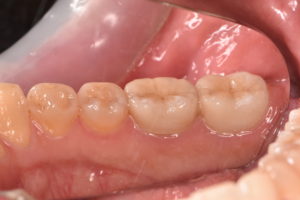

歯冠修復後

ジルコニアセラミッククラウン 132,000円(支台築造、仮歯代含む)

また根管治療後に適合の良い、再感染の起こりにくいジルコニアセラミッククラウンでしっかり再感染を防ぐことが根管治療の予後を左右します。

根管治療とともに歯冠修復物の精度がその歯の予後にとって極めて重要であると言えます。

根管治療と歯冠修復物の精度を高めるために当院ではマイクロスコープや高倍率ルーペを使用しています。